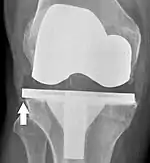

Loosening

Loosening of the prosthesis can be indicated on X-ray by thin radiolucent spaces around the implant, or more obviously by implant displacement.[53]

Post-operative evaluation

Knee replacement is routinely evaluated by X-ray, including the following measures:

- FFC: frontal femoral component angle. It is typically regarded as optimal when being 2–7° in valgus.[60]

- FTC: frontal tibial component angle, which is regarded as optimal when being at a right angle. A varus position of more than 3° has generally been found to increase the failure rate of the prosthesis.[60]

- Anterior femoral notching (the femoral component causing reduced thickness of the distal femur anteriorly), seems to cause an increased risk of fractures when exceeding about 3 mm.[61]

- LTC: lateral (or sagittal) tibial component angle, which is ideally positioned so that the tibia is 0–7° flexed compared to at a right angle with the tibial plate.[60]